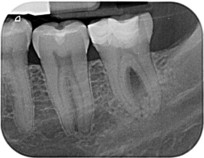

Zahn 38 Aufhellung in der Furkation 07/2012

Zustand nach Wurzelkanalbehandlung 07/2012

Beachte Seitenkanal mesiale Wurzel mit Sealerpuff.

Kontrollbild 05/2013